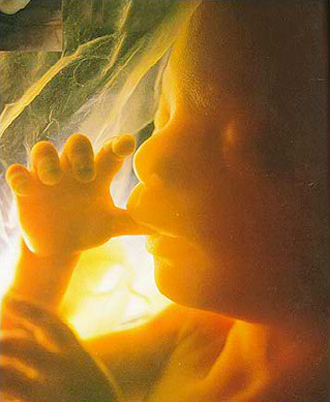

- 중기 정밀 초음파

(태아 내부장기 및 근골격 기형 등을 검사)